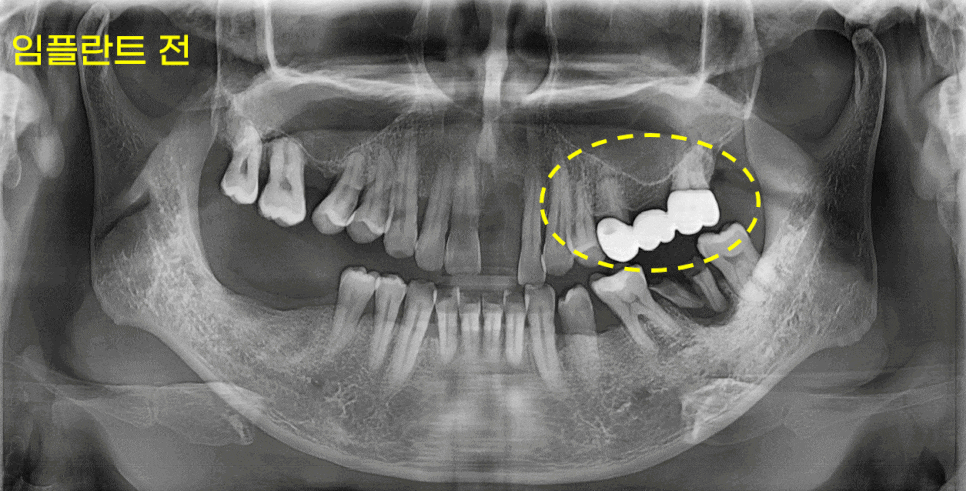

첫번째, 임플란트 한계와 부작용을 설명해주는 병원인지?

하남 임플란트 치과에서 상담 받으실 때

"임플란트 한계"도 언급해주는 곳을 선택하셔야합니다.